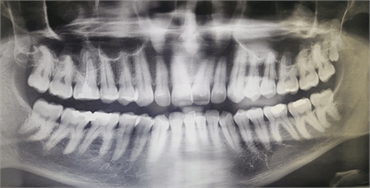

Most distomolars are discovered incidentally during dental X-rays. Dentists may recommend panoramic radiographs or 3D imaging like CBCT scans for precise visualization and treatment planning.

Key diagnostic indicators include:

• Tooth-like structures behind the third molars

• Impacted or unerupted teeth in the distal region

• Asymmetry or shifting of existing molars